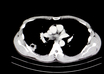

CT Imaging of the 2019 Novel Coronavirus (2019-nCoV) Pneumonia

M3 India Newsdesk | Feb 11, 2020